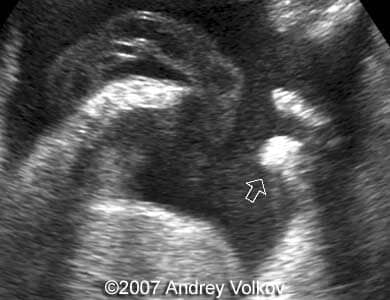

A 26-year old G1P0 from a nonconsanguineous couple (husband 35 years old), with noncontributive history, presented to our unit at 30 weeks of pregnancy. Our ultrasound examination revealed following findings:

• Lobar holoprosencephaly;

Images 1, 2: 30 weeks of pregnancy; Image 1 shows cloverleaf shaped fetal skull. Image 2 shows transverse scan through the fetal skull with lobar holoprosencephaly.